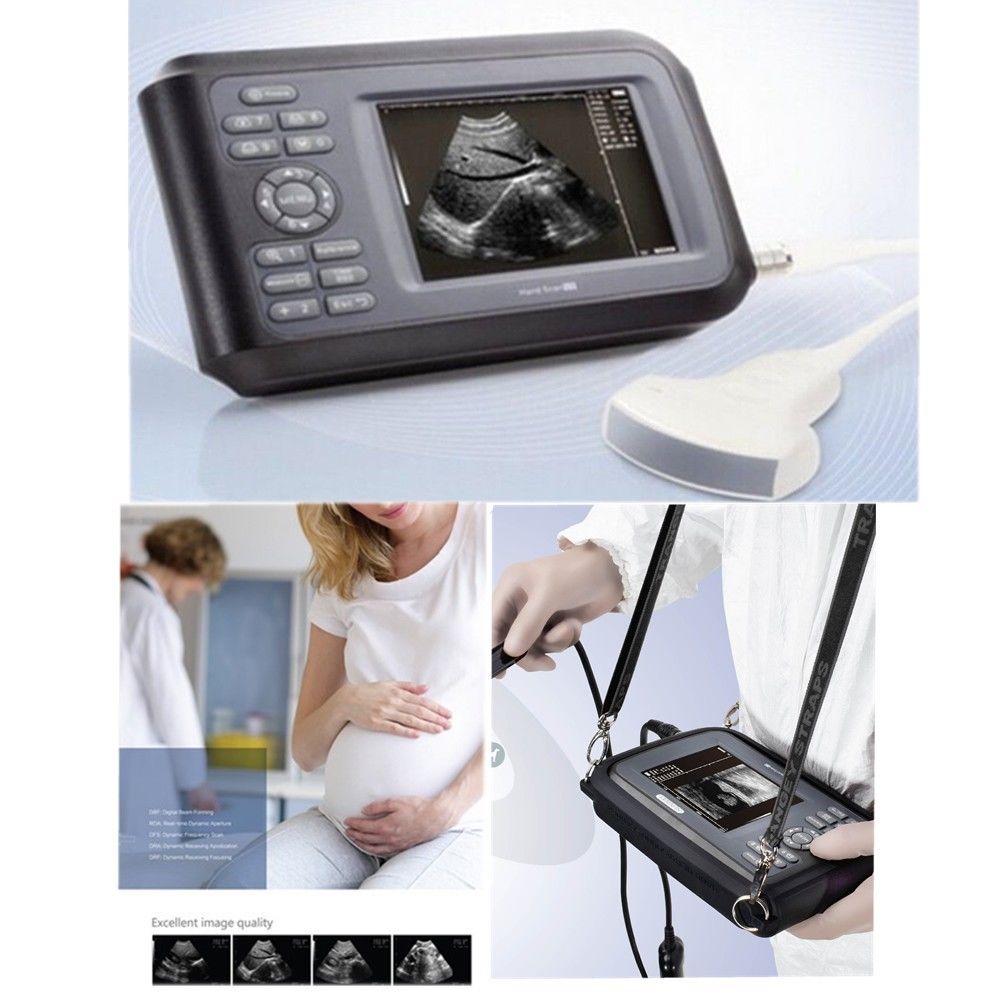

DIAGNOSTIC ULTRASOUND MACHINES FOR SALE

Laptop Ultrasound Machine Portable Medical Scanner with Transvaginal Probe USA 6945040100362

Sale price$ 1,798.00

Regular price$ 1,918.00